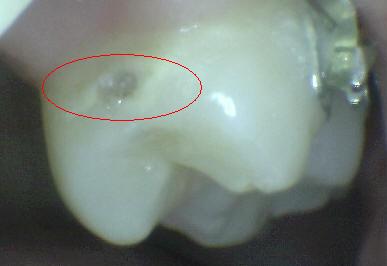

Código 5

(Caries Severa): Cavidad

detectable con dentina visible hasta la mitad de la superficie. |